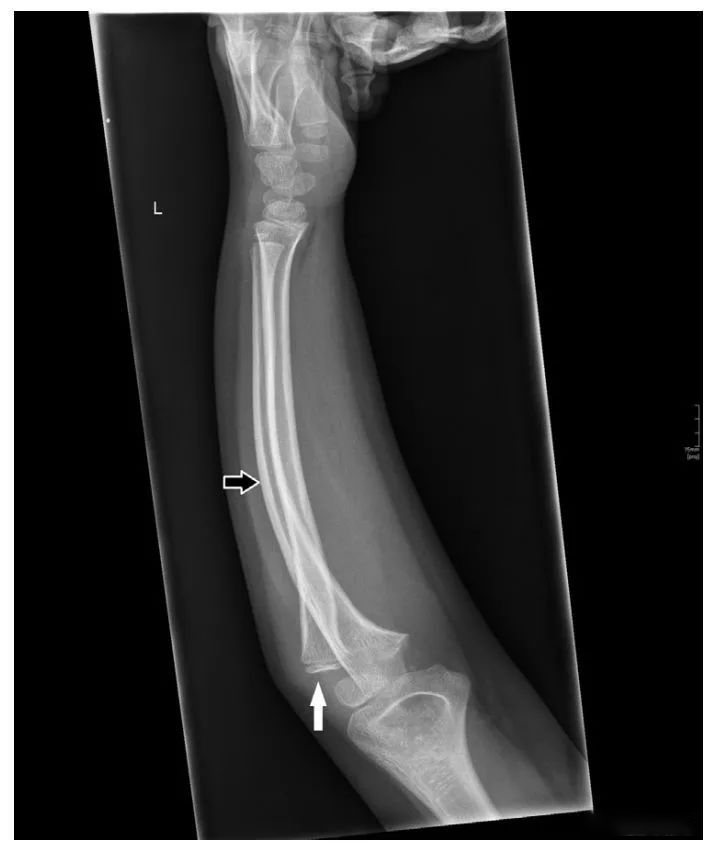

图 二 这名 8 岁女童的前臂侧位片显示桡骨头后脱位 (实心白色箭头) 和尺骨弯曲变形 (空心白色箭头),这与骨骼发育不成熟的患儿的 Monteggia 骨折脱位相一致。这是一种 BadoⅡ 型 Monteggia 骨折脱位。

图二

图三 这是一例 17 岁的 BadoⅠ 型 Monteggia 骨折脱位的病例,伴有桡骨头前脱位 (黑色箭头) 和尺骨近段横形骨折 (白色箭头)。

图三